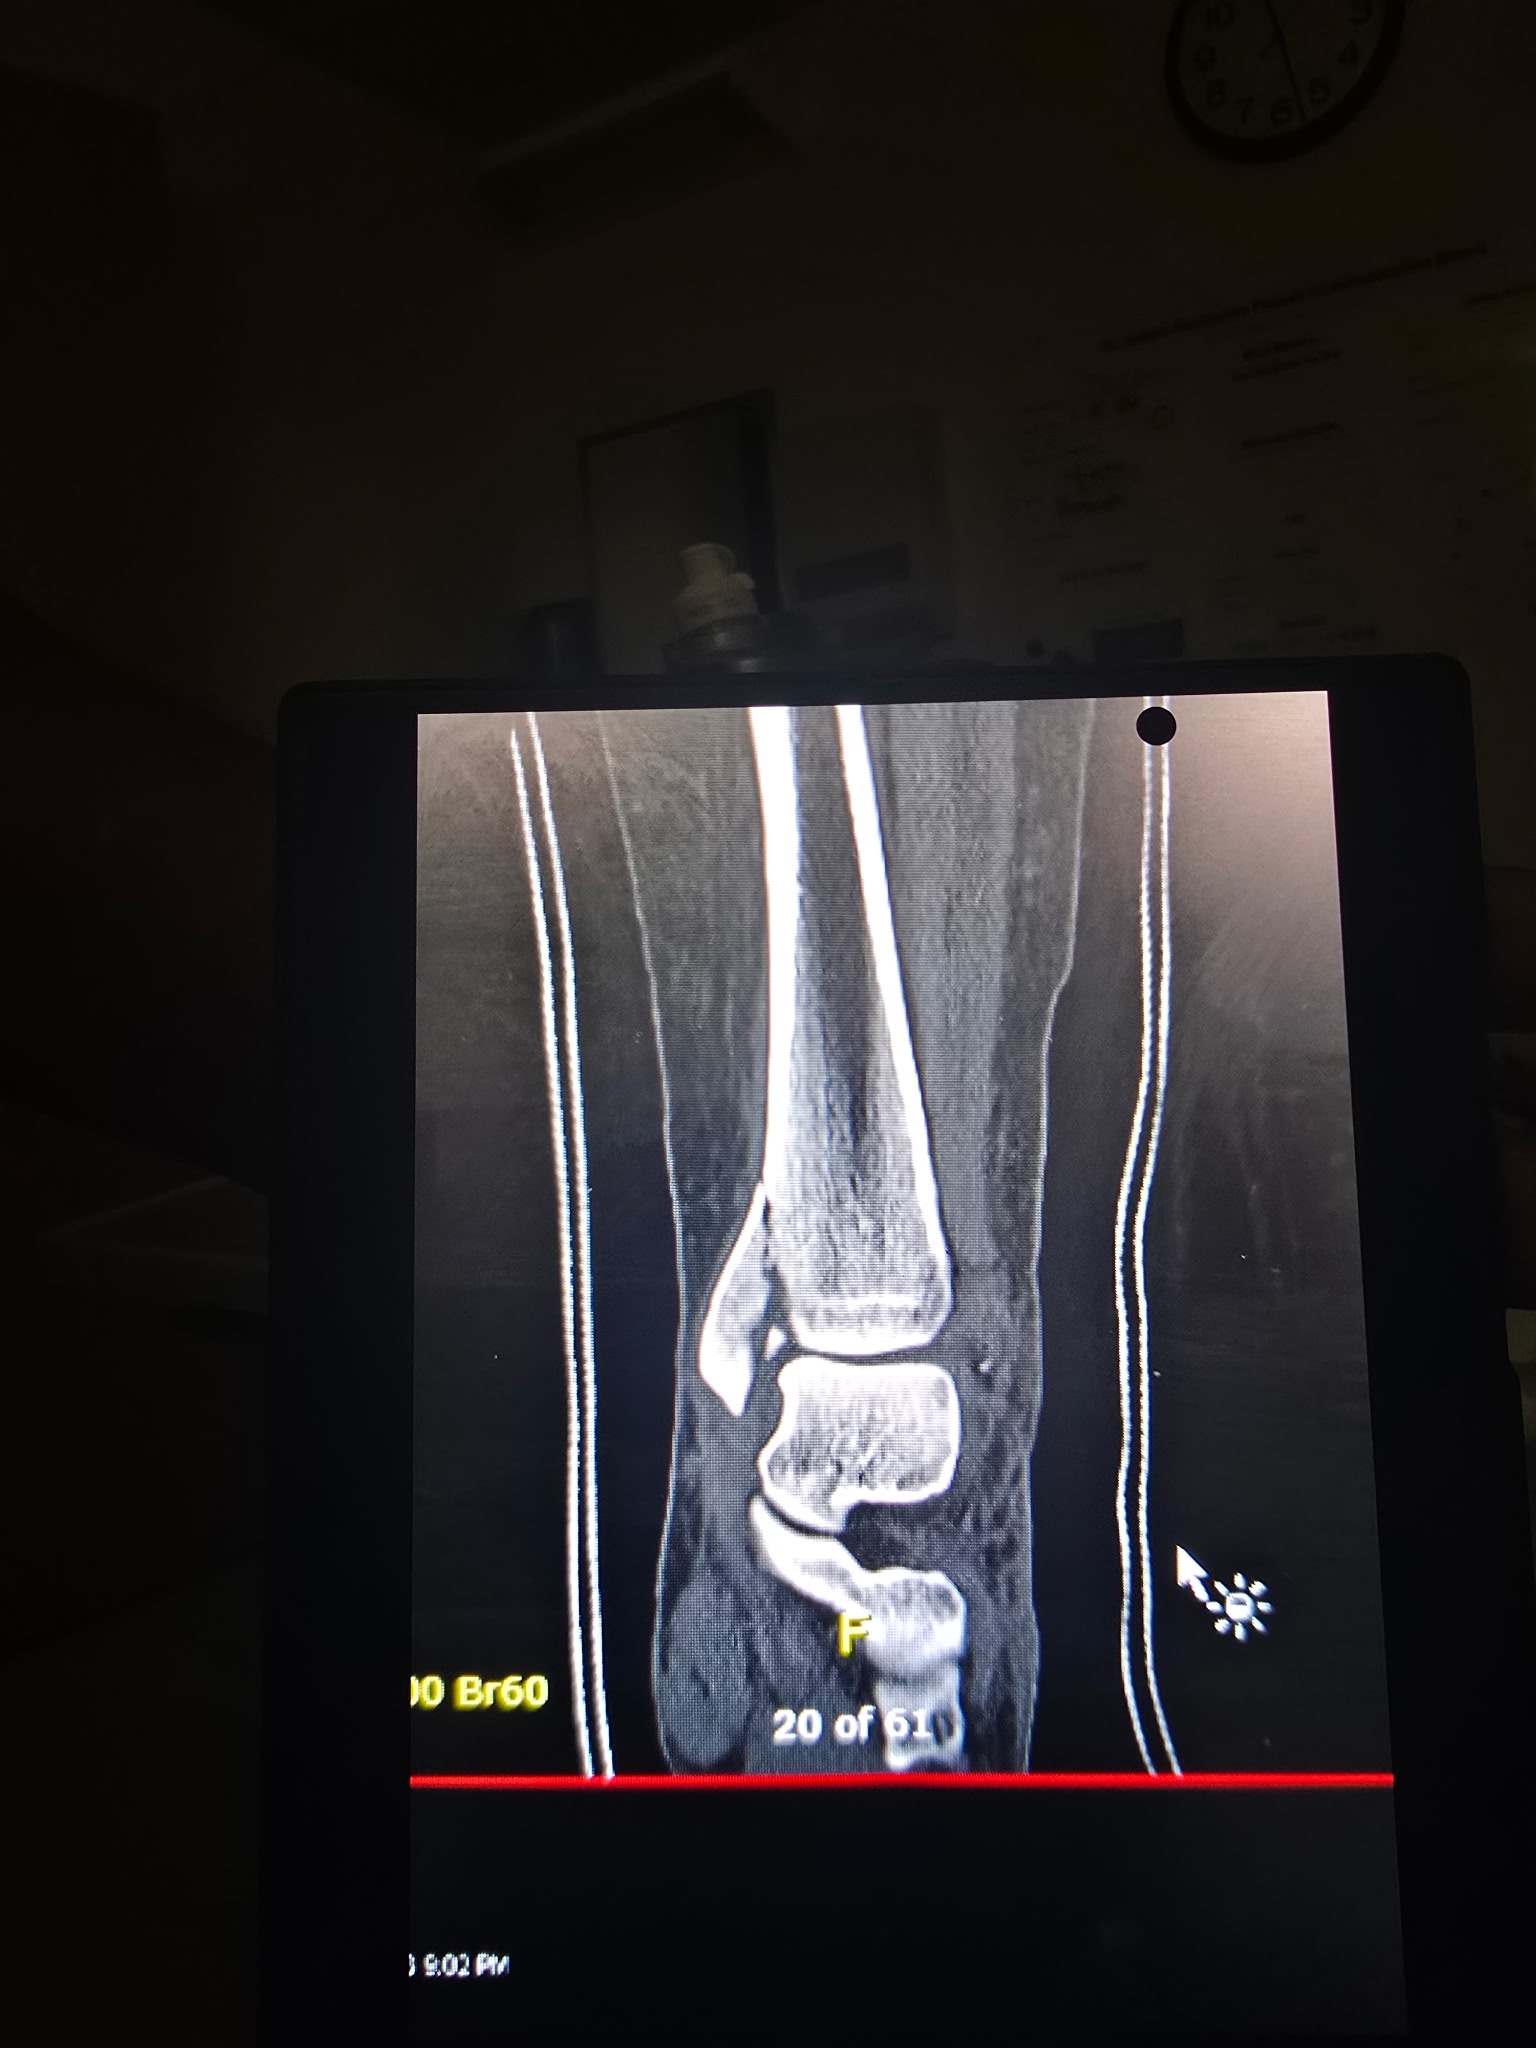

On 01/10/2026, Chelsea slipped and fell on the ice in her driveway, causing a dislocated ankle along with fractures to her ankle and leg. She went to the ER the same day, where the dislocation was stabilized, and she was admitted to the hospital. On 01/11/2026, she underwent her first surgery, where a rod, plate, and screws were placed to stabilize her injuries.

At her follow-up appointment with her orthopedic surgeon on 01/14/2026, it was determined that there had been too much swelling during the first surgery, and she would need a second surgery to place an additional plate on the back of her ankle. That second surgery was completed on 01/15/2026.